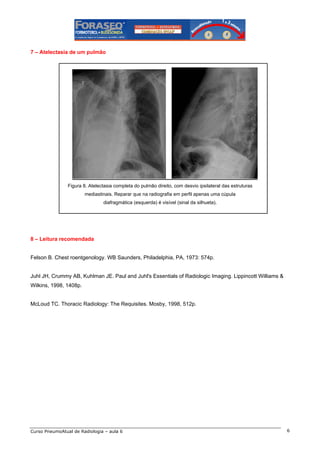

Figura 5. Atelectasia do lobo médio. Na radiografia em PA o único sinal é indireto: aproximação dos

vasos pulmonares (setas). No perfil há opacidade triangular projetada sobre a imagem cardíaca,

com aproximação das fissuras horizontal e oblíqua (setas). Na atelectasia da língula os sinais

são os mesmos, mas do lado esquerdo.